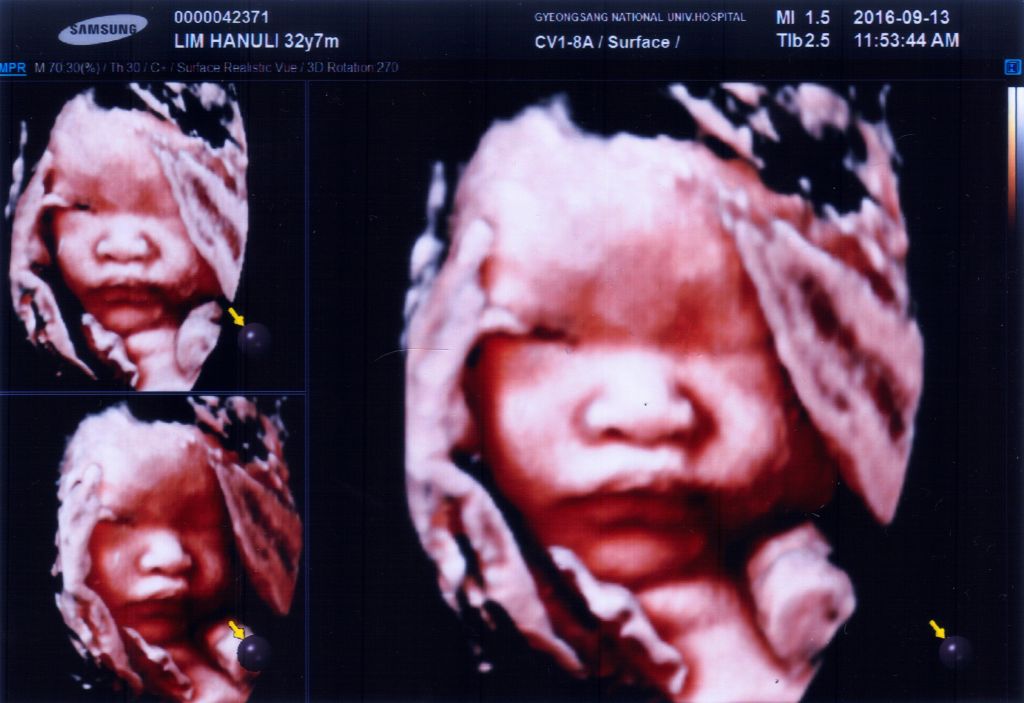

추석 직전에 별이 어멈 대상포진으로 대학병원에 가서 찍은 사진이에요.

저희가 다니는 병원보다 장비가 좋아서 그런지 사진도 잘나왔네요^^ 하지만 저 사진 두장이 거의 9만원이라는건 ㅎㄷㄷ